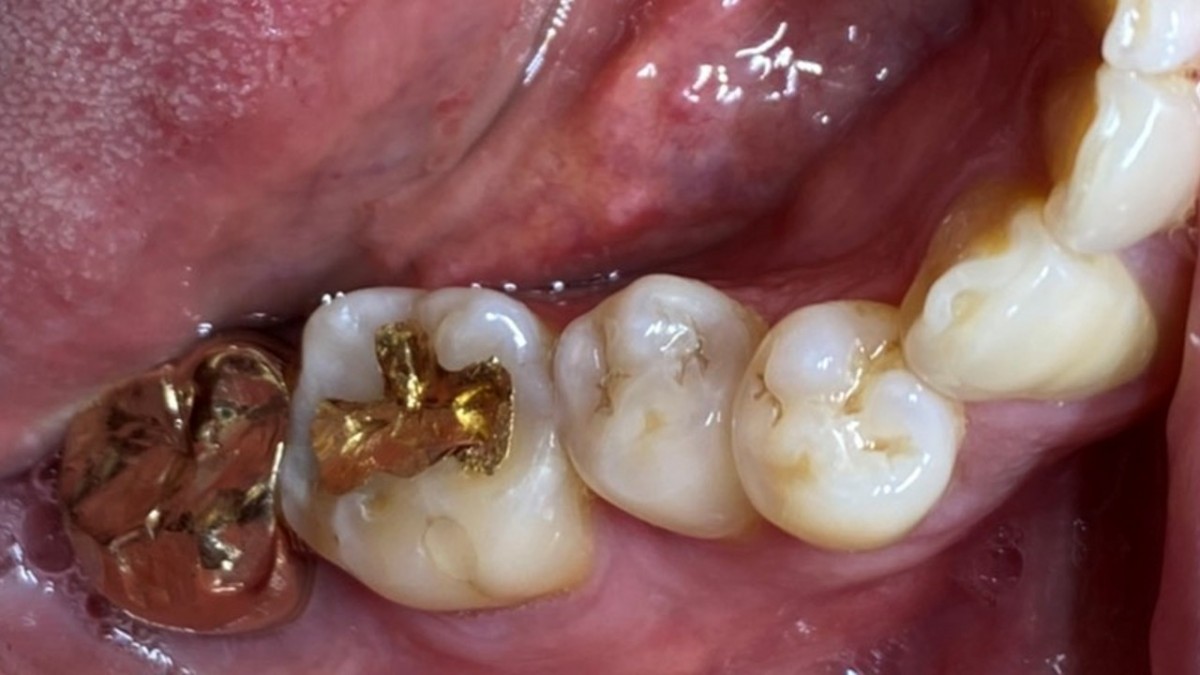

A 47-year-old male patient had a crown with an ill-fitting margin and crack-tooth syndrome in the lower 2nd molar. No systemic issue.

▲extraction

▲Arum Dentistry NB1 5*10